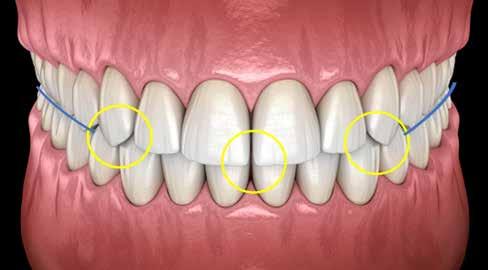

Több taktika is segíthet az összetett tömegek rétegződésének kezelésében ezekben a forgatókönyvekben. A palatális stent használata ennek egyik kiszámítható módja (1–4. ábra). Ennél a technikánál a törött területről egy modellen wax-up vagy mock-up készül, és egy gyurma PVS stentet vagy indexet állítanak elő. Ebből egy vékony réteg erős, félig áttetsző kompozit – tipikusan nano- vagy mikrohibrid – kerül a stentre, amely a szájpadlásfelületet reprodukálja. Ezt követően különböző opacitású és transzlucenciájú kompozitrétegeket rétegeznek az arcfelületre, így létrehozva egy zökkenőmentes restaurációt (1. a–c. ábra). Mivel viaszfelvételből készül, az okkluzális tényezőknek jól ellenőrizhetőnek kell lenniük. Ennek a technikának az a hátránya, hogy szükség van egy mock-upra, akár intraorálisan, akár egy modellen történő wax-up segítségével. Ez időigényes lehet, és második időpontot igényelhet, amely nehéz vagy nem praktikus, különösen gyermek- vagy sürgősségi páciensek esetében. Ezenkívül kis törések esetén a kompozittömegek behelyezése nehezebben megoldható, mint nagyobb törések esetén. Egy alternatív megközelítés az „üres vászon technika”, amely gyorsított polikromatikus helyreállítást biztosíthat kisebb törések, sürgősségi esetek vagy gyermekpáciensek esetében. Ez egy kromatikus mikrohibrid alapot használ, amelyet szükség esetén tinták vagy opakok követnek, és egy vékony réteg akromatikus mikrokitöltésű kompozit fed. A cél a törés elfedése és egy élethű, a környező fogazat transzlucenciájának és opacitásának megfelelő helyreállítás biztosítása.

Az erős opaleszcencia jellemzően erős ellenopaleszcenciával jár. A 2. ábra szemléltetésképpen a 9. fog törésének metszőleges szélén megfigyelhető inceszális halót mutatja. A #8-as fogon egy hagyományosabb opaleszcencia/kontrapaleszcencia mintázat látható.